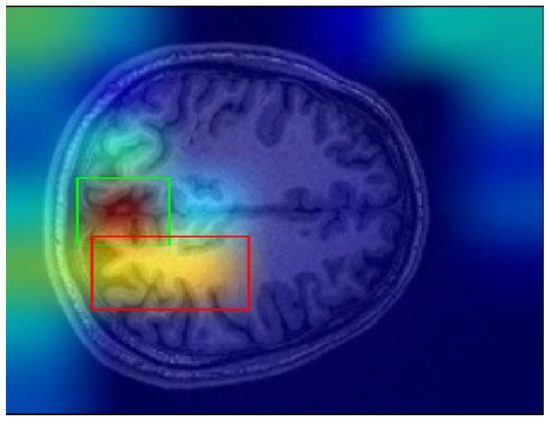

Finally, one of the most important challenges encountered in this study involves the Grad-CAM explanations. Grad-CAM visualizations sometimes yield misleading results, particularly when determining the most meaningful bounding boxes. Bounding boxes are selected based on a threshold applied to the Grad-CAM scores, and regions above the threshold values are considered significant regions. However, this threshold was determined through trial and error, and this can cause ambiguity in some cases. For instance, as shown in Figure 11, there may be multiple bounding boxes with comparable importance. While the red box surpasses the threshold and is selected, the green box, which may also be significant, is excluded. Determining which region would enhance model performance remains a challenging problem.

Figure 11. Sample Grad-CAM result.

Applsci 15 01717 g011